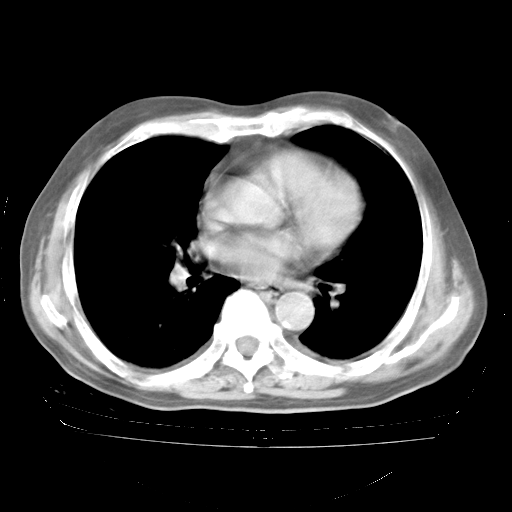

4月28日肺部CT——再次出现类似去年5月9日——透光度降低,“间质性”改变。

4月28日肺部CT——再次出现类似去年5月9日——磨玻璃样、间有“粟粒样”改变。

4月28日肺部CT